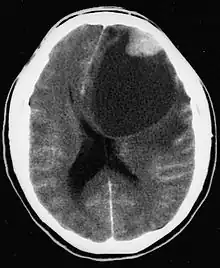

CT scan of a brain with pleomorphic xanthoastrocytoma. The classic radiographic appearance is one of a superficially situated tumor, here a mural nodule, associated with an underlying cyst.